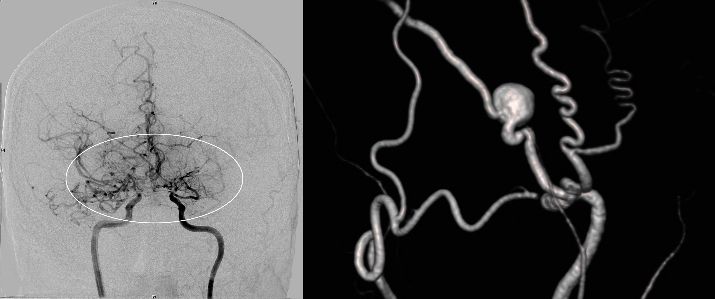

Angiografie einer Moymoya

Auf dem Bild mit einer Gefäßdarstellung “Angiographie” kann man die dünnen Kollateralen (Wolken-ähnliches Bild) um die Gefäßengstelle am Ende der inneren Halsschlagader erkennen.

Die konventionelle cerebrale Angiographie ist die wichtigste Untersuchung zur Diagnosestellung der Moyamoya Krankheit. Diese Untersuchung ist zu vergleichen mit einer Herzkatheteruntersuchung, eben nur mit Darstellung der Hirnarterien. Bei Moyamoya-Patientinnen und Patienten werden, im Gegensatz zu Routineuntersuchungen bei anderen cerebralen Erkrankungen, selektiv die vordere und hintere Zirkulation des Gehirns dargestellt, sowie auch die Versorgung der extrakranialen Gefäße. Diese umfassende Darstellung ist besonders wichtig, um die vollständige Ausdehnung der Erkrankung zu erfassen und alle möglicherweise veränderten Blutflüsse im Gehirn zu verstehen. Je nach Befund werden die Engstellen der Hirnarterien, sowie auch mögliche begleitende Veränderungen selektiv hochauflösend dreidimensional dargestellt. Es ist wichtig zu erwähnen, dass die Moyamoya Krankheit nicht über eine Katheterintervention (Ballonaufweitung der Engstelle) behandelt werden kann und darf. Dies haben mehrere Studien gezeigt.

Angiographie beidseitige Moyamoya Krankheit

Konventionelle Angiographie eines Patienten mit beidseitiger Moyamoya Krankheit (links). 3-dimensionale Darstellung eines Aneurysmas einer jahrelang stark beanspruchten Spontan-Kollaterale (rechts).